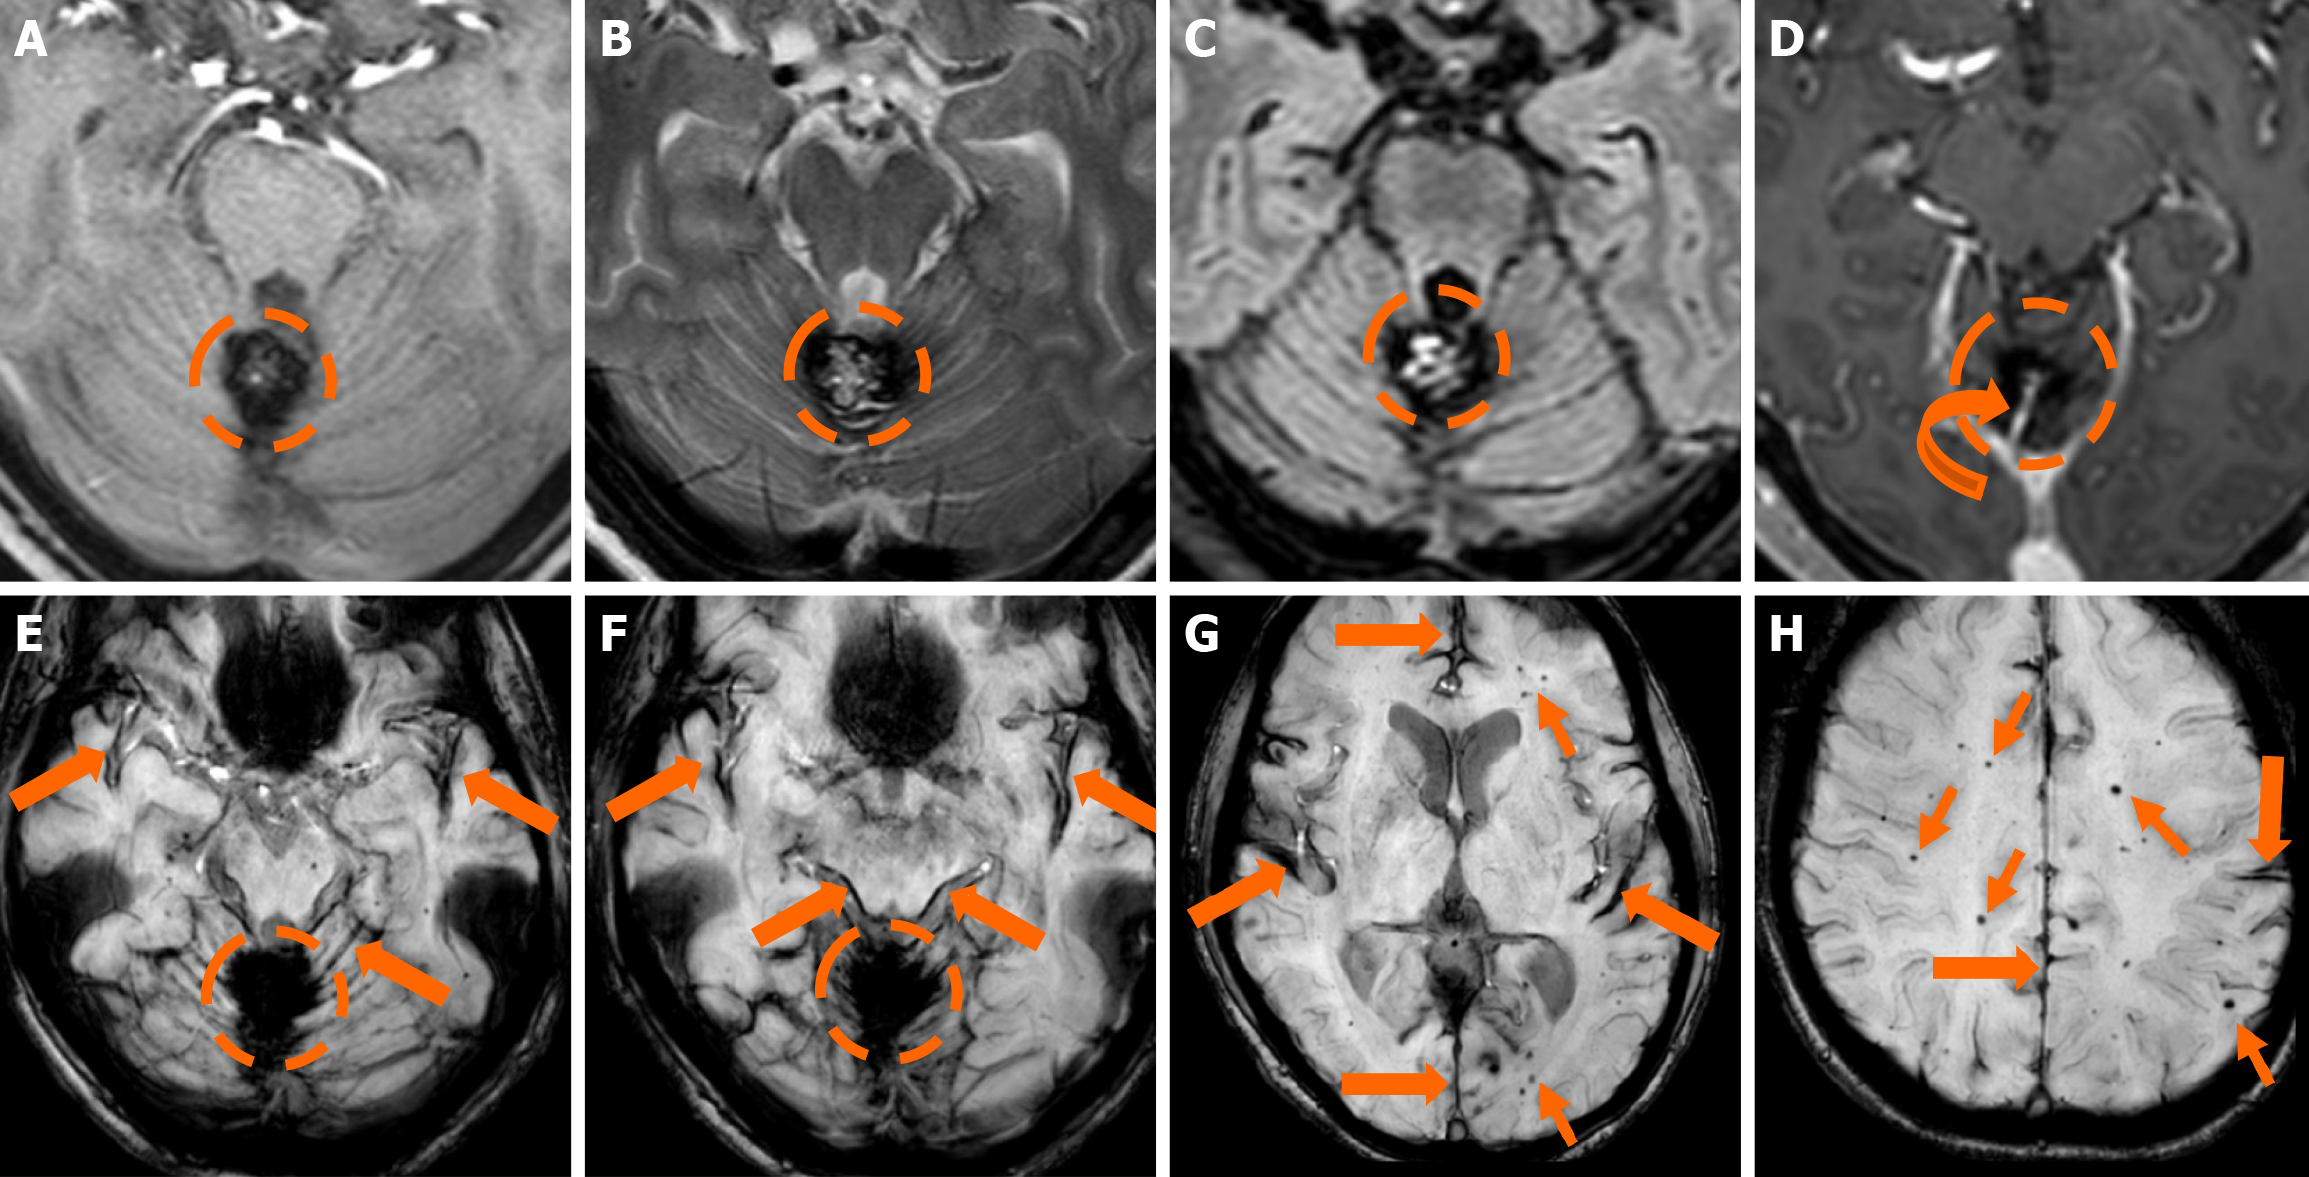

The clinical applicability of the Zabramski classification is still being investigated. A retrospective cohort study evaluating the imaging evolution and clinical trajectory of 255 untreated patients with sporadic CMs over a follow-up period of approximately five years provided evidence that the Zabramski classification may facilitate risk stratification and contribute to treatment planning, particularly in determining the necessity for surgical intervention[89]. Furthermore, a recent study by Saari et al[88] established an association between the radiological characteristics of the Zabramski classification and their clinical relevance, emphasizing that type I lesions have a higher likelihood of becoming symptomatic. Nikoubashman et al[90] suggested an additional category (type V lesions) accounting for cavernomas presenting with gross extralesional hemorrhage. Various examples of CMs on CTs and MRIs, including familial cerebral CM cases, are shown in Figures 4, 5 and 6.

Imaging findings in coexistent DVAs and CMs will be the combination of those described for each malformation separately. Awareness of the possibility of their coexistence may prove invaluable in clinical practice. This is because recognition of a DVA close to a brain hemorrhage may raise suspicion for an underlying CM as the most likely etiology. Additional examinations and follow-up imaging following hematoma resolution will further enhance diagnostic confidence. Figures 8, 9, 10 and 11 illustrate clinical examples in which identifying the synchronous presence of a DVA adjacent to a brain hemorrhage (or suspected brain hemorrhage) enabled the diagnosis of a probable underlying CM as the most likely etiology, thereby avoiding unnecessary examinations or interventions.